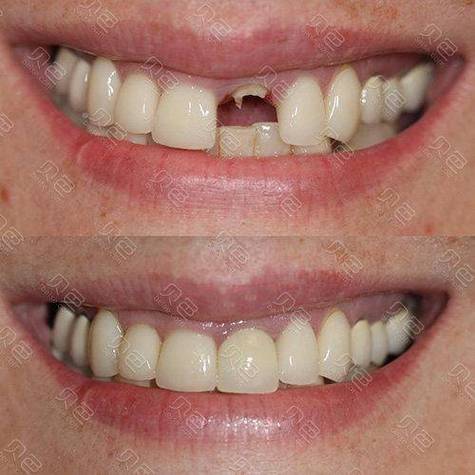

- 功能恢复良好: 修复后,种植牙能够正常咀嚼,无疼痛、不适,发音正常,美观效果满意。